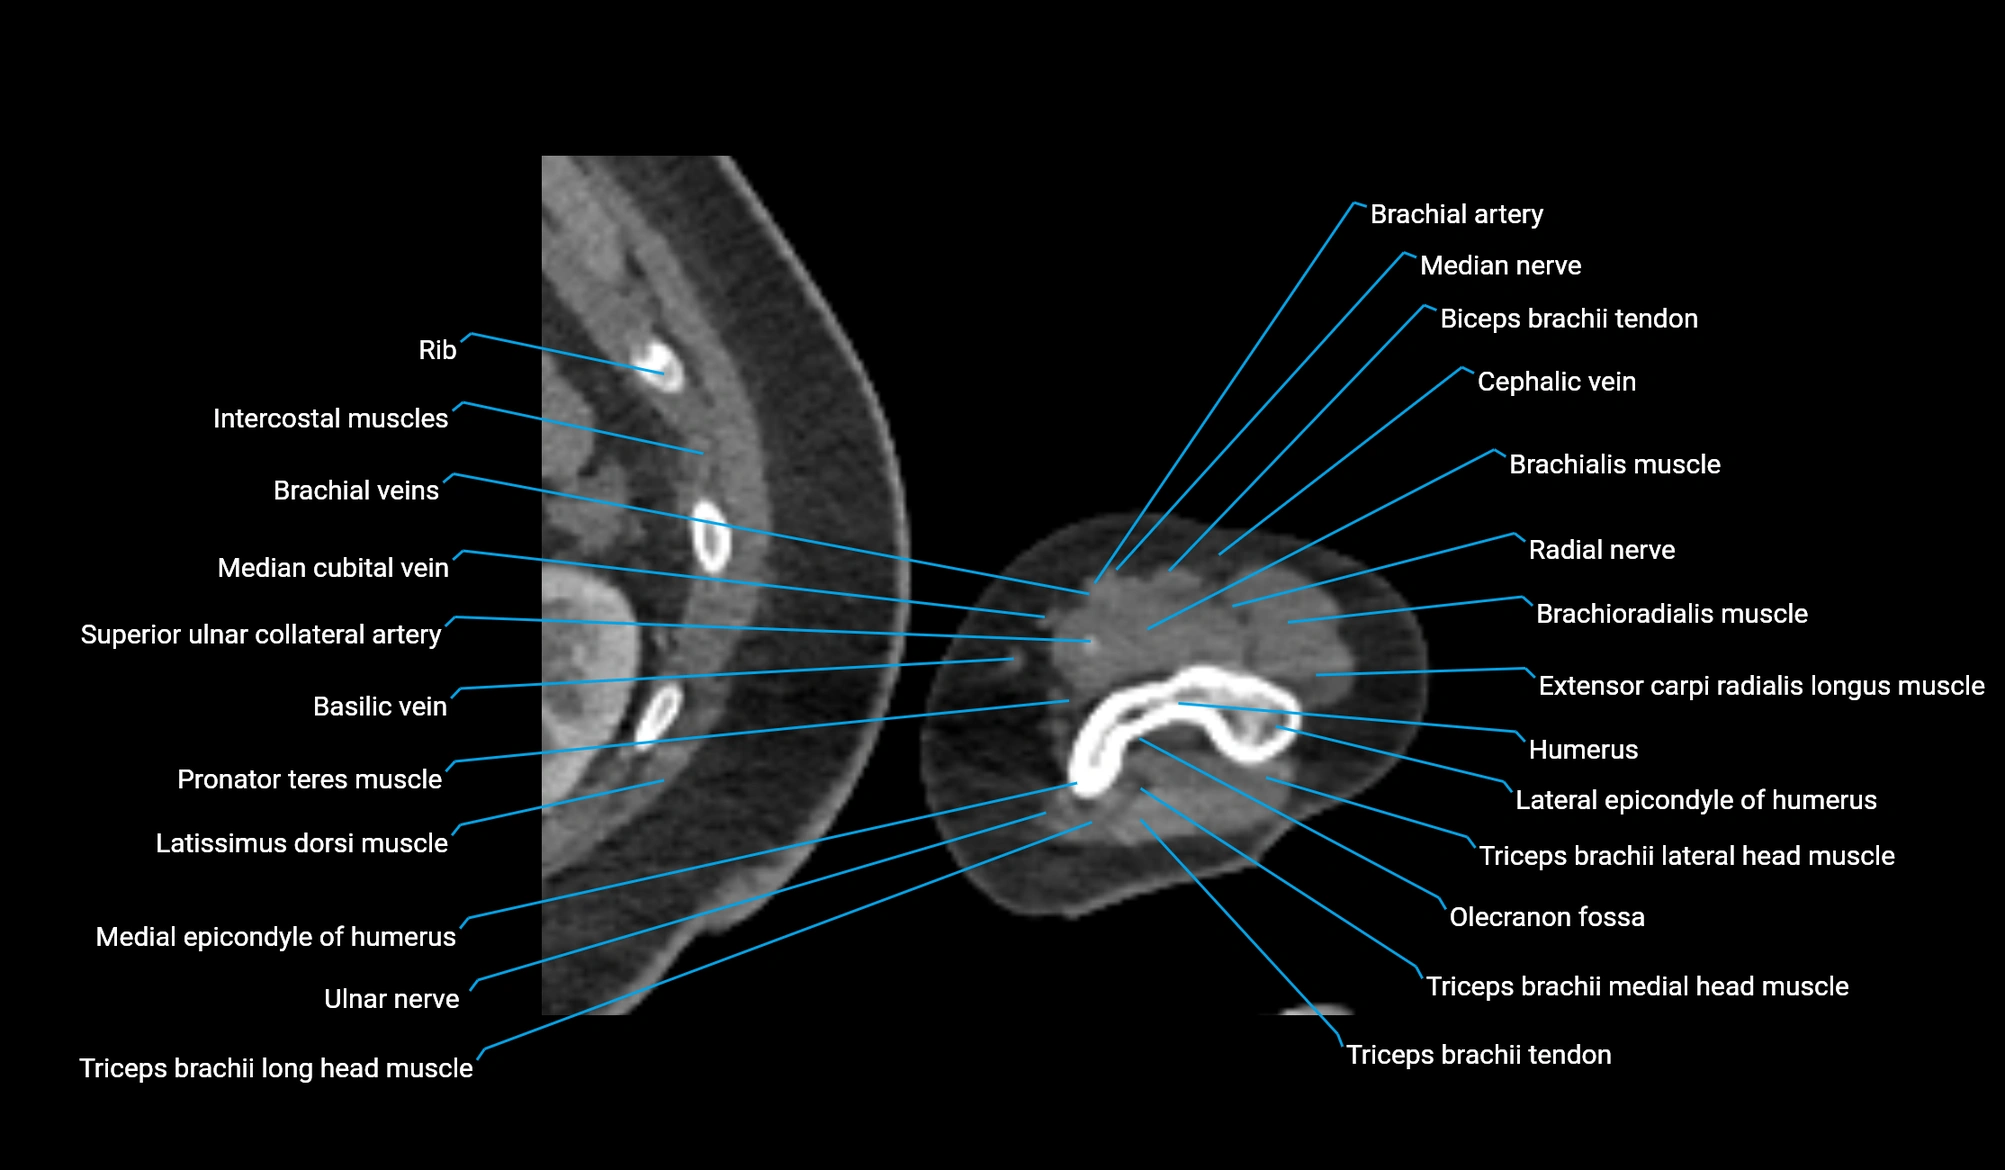

- Brachial artery

- Brachialis muscle

- Brachioradialis muscle

- Cephalic vein

- Extensor carpi radialis longus muscle

- Lateral epicondyle of humerus

- Lateral head of triceps brachii muscle

- Long head of triceps brachii muscle

- Medial epicondyle of humerus

- Medial head of triceps brachii muscle

- Median cubital vein

- Median nerve

- Olecranon fossa

- Pronator teres muscle

- Radial nerve

- Superior ulnar collateral artery

- Triceps brachii tendon